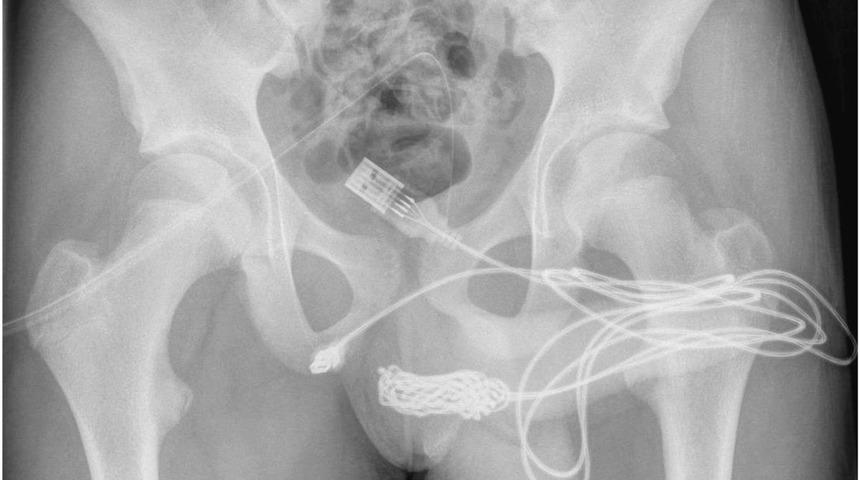

İngiltere’de yaşayan ve ismi açıklanmayan 15 yaşındaki bir erkek çocuk cinsel organının boyunu ölçmek için penisine USB kablosu yerleştirdi. Ancak USB kablosunu penisinden çıkaramaması ve idrarında kan görülmesi üzerine annesi tarafından hastaneye kaldırıldı. Doktorlar yabancı cismi ameliyatla çıkartmayı başardı.

İngiltere’de yaşayan 15 yaşındaki bir erkek çocuk düğümlediği tam 5 metre uzunluğundaki USB kablosunu cinsel organına yerleştirdi. Cinsel deney yaptığını ifade eden çocuk kabusu yaşadı. USB kablosunun cinsel organına zarar vermesi üzerine idrarında kan görmeye başlayan çocuk annesi tarafından hastaneye kaldırıldı. Doktorlara durumu itiraf etmeden önce annesinin odadan çıkmasını bekleyen çocuk, 5 metrelik USB kablosunu cinsel organına yerleştirdiğini söyledi.

Doktorlar Science Direct raporunda olaya ilişkin olarak, “USB kablosunun iki distal portunun dış üretral kanaldan dışarı çıktığı ve düğümlü telin orta kısmının üretra içinde kaldığı tespit edildi. Hasta, ruh sağlığı bozukluğu öyküsü olmayan, aksi halde zinde ve sağlıklı bir ergendi." ifadelerine yer verildi. Doktorlar oluşan düğüm miktarı nedeniyle kabloyu metal bir çubukla çıkartamadılar. Bu nedenle çocuk acilen ameliyata alındı.

Kateterler takılıyken sıkışan kabloya erişim sağlamak için cinsel organları ve anüsü arasına bir yerleştirme yapıldı. Prosedürü açıklayan doktorlar, "Elle gelen yabancı cisim üzerinde uzunlamasına bir penoskrotal kesi yapıldı ve daha derin dokularda dikkatli bir diseksiyon yapıldı ve bulbospongiosus kasını ayırdı. Telin her iki ucu da dış üretral kanaldan başarıyla çıkarıldı." dedi.

Ameliyatın ardından iki haftalık iyileşme sürecisini tamamlayan çocuk taburcu edilerek evine gönderildi. Bununla birlikte çocuğun uzun süreli hasarın olup olmadığını tespit edilmesi için sık sık rutin kontrollerden geçeceği belirtildi.